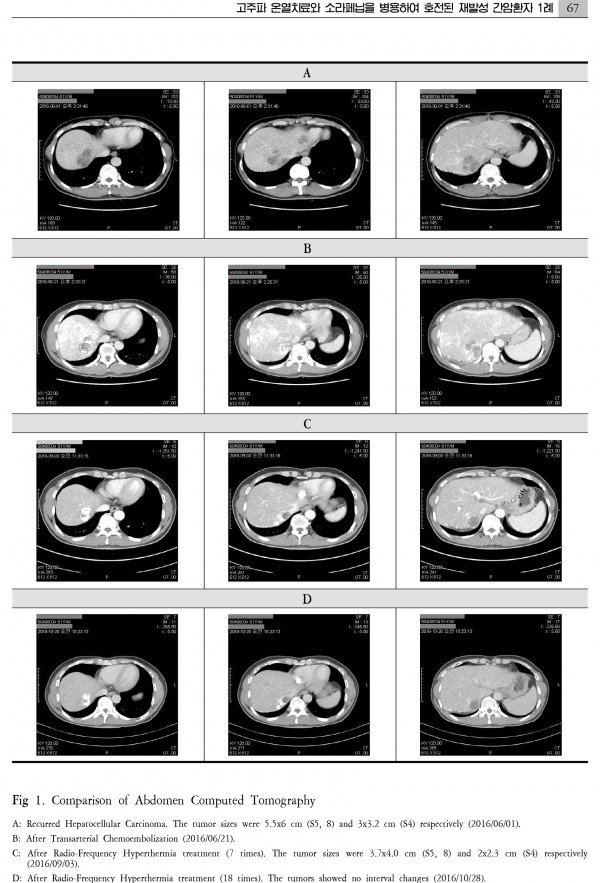

간암 치료 대전대학교 논문